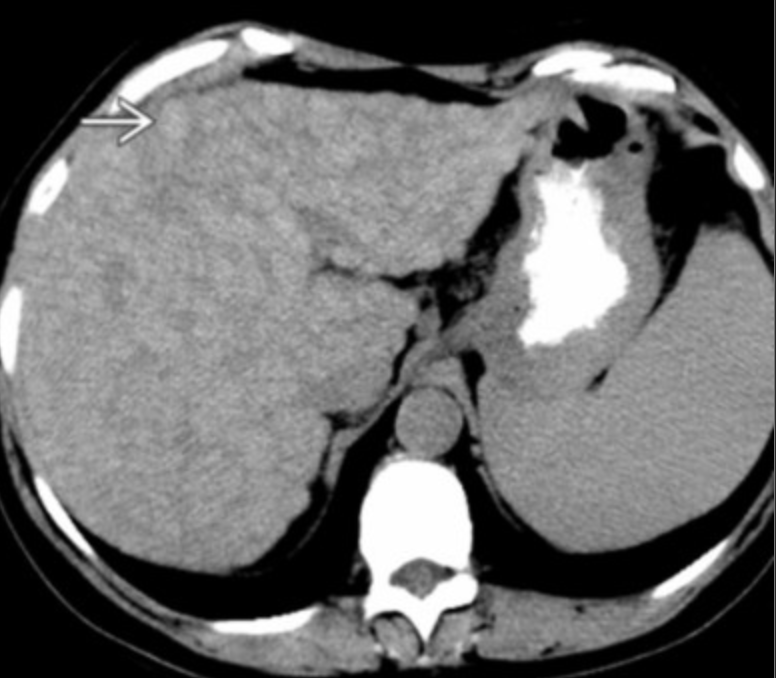

Hemangioma

• Commonly peripheral in liver

• CT = non-specific hypoattenuating liver mass